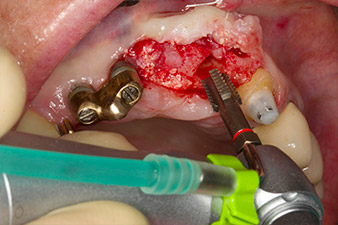

Following primary healing, the soft tissues were shaped using the basally lined bridge. Two months later the site was exposed by a slightly palatal alveolar ridge incision (Fig 2). The dimensions of the alveolar bone proved to be sufficient at position 22. Figures 2 and 4 show the preparation of the implant bed, the tapping and the implantation using Implantmed.

The new implantology motor was used with the appropriate W&H surgical contra-angle handpieces.